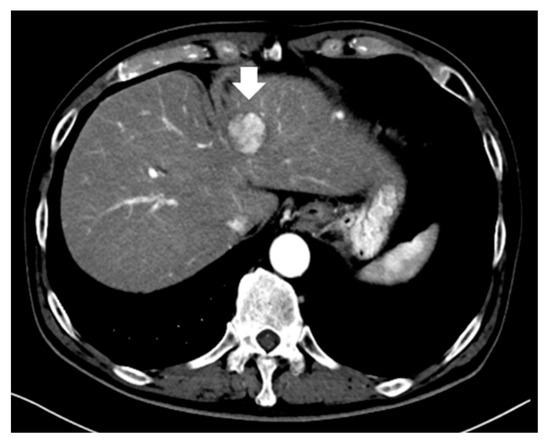

- Kawamura, Y.; Ikeda, K.; Hirakawa, M.; Yatsuji, H.; Sezaki, H.; Hosaka, T.; Akuta, N.; Kobayashi, M.; Saitoh, S.; Suzuki, F.; et al. New classification of dynamic computed tomography images predictive of malignant characteristics of hepatocellular carcinoma. Hepatol. Res. Off. J. Jpn. Soc. Hepatol. 2010, 40, 1006–1014. [Google Scholar] [CrossRef]

- Kawamura, Y.; Ikeda, K.; Seko, Y.; Hosaka, T.; Kobayashi, M.; Saitoh, S.; Kumada, H. Heterogeneous type 4 enhancement of hepatocellular carcinoma on dynamic CT is associated with tumor recurrence after radiofrequency ablation. AJR Am. J. Roentgenol. 2011, 197, W665–W673. [Google Scholar] [CrossRef]

- Shimizu, R.; Tamai, H.; Mori, Y.; Shingaki, N.; Maeshima, S.; Nuta, J.; Maeda, Y.; Moribata, K.; Muraki, Y.; Deguchi, H.; et al. The arterial tumor enhancement pattern on contrast-enhanced computed tomography is associated with primary cancer death after radiofrequency ablation for small hepatocellular carcinoma. Hepatol. Int. 2016, 10, 328–339. [Google Scholar] [CrossRef] [PubMed]